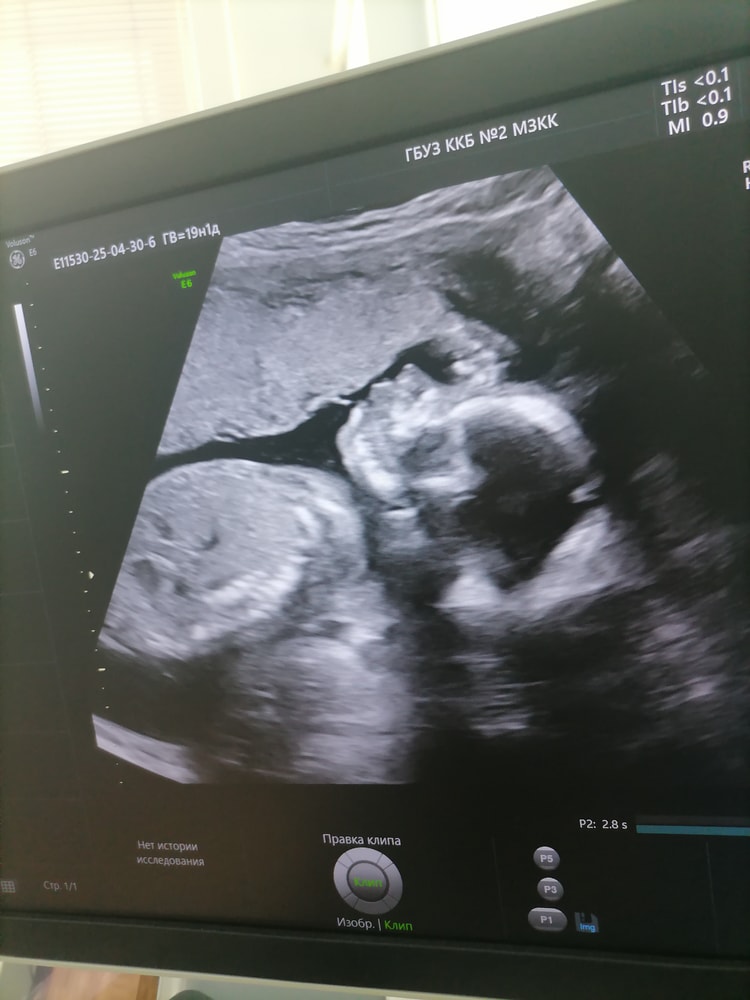

Прошли мы второй скрининг, по развитию идём в день пдм. Хотя на первом скринге опережали на 1 день. Вес у нас 281гр в 19 недель, пол в конверте, гендер пати будет, розовый кружочек это на первом узи пол предположили, ждём-ссс. Внешне по узи похожа на меня🥰